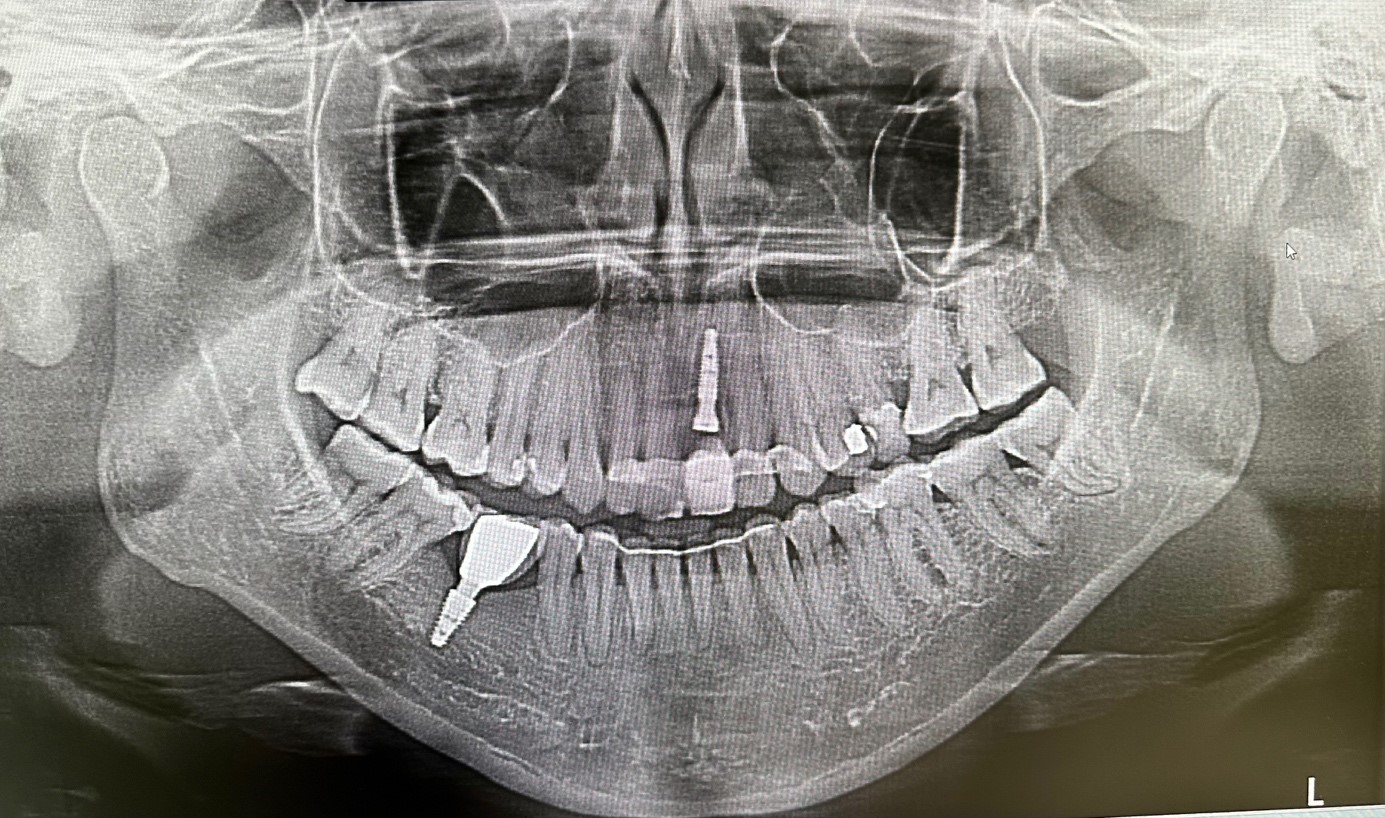

Zdjęcie RTG po usunięciu zęba i jednoczasowym założeniu implantu

Chirurgia: dr n.med. Ewa Zawiślak

Protetyka: dr n.med. Ewa Zawiślak